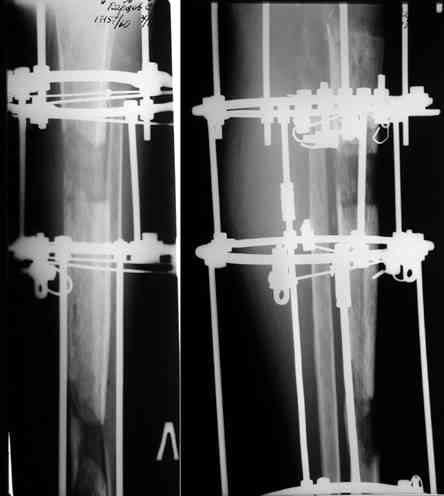

После нескольких некрэктомий, проведения аутодермопластики и заживдения ожоговой раны через 2 месяца после травмы произведен открытый остеосинтез левой бедренной кости штифтом и пластиной (деротационной) [image 01, 02]. Через 1 год и 7 месяцев после травмы у больного диагностированы ложный сустав и хронический остеомиелит левой бедренной кости. Произведено удаление металлических фиксаторов, секвестрэктомия и остеосинтез бедренной костивнешним двухплоскостным стержневым аппаратом [image 03, 04] .